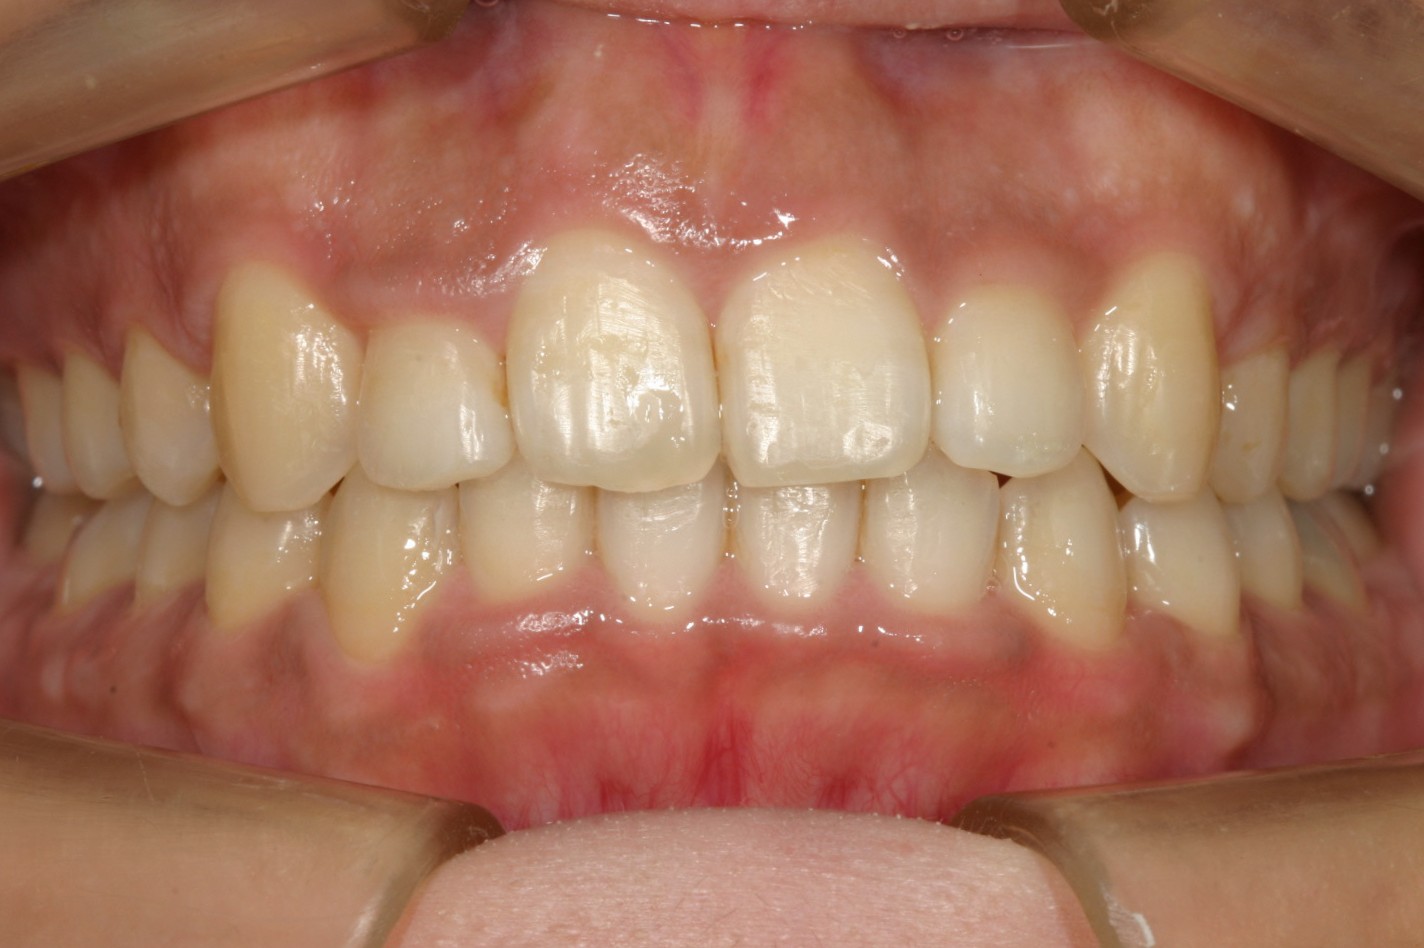

マルチループを装着5ヵ月後です。殆ど綺麗に改善しています。

下顎は殆どすでに改善しています。

この様に綺麗に改善致しました。

オーバージェットも綺麗に改善しました。